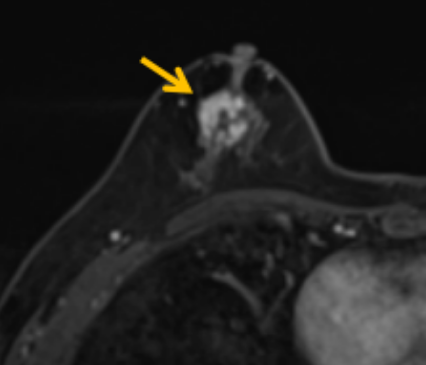

陳寶瑩評估圖像后發(fā)現(xiàn)病變?yōu)閮H僅在磁共振增強(qiáng)時(shí)顯示,為非腫塊樣病變,比較散,必須取得足夠多的組織才能確保病理檢查的準(zhǔn)確性,常用的核芯針活檢獲取的組織較少,因此最終確定了磁共振引導(dǎo)下行真空輔助抽吸旋切活檢。取得患者及家屬認(rèn)可后,陳寶瑩帶領(lǐng)團(tuán)隊(duì)開始進(jìn)行術(shù)前準(zhǔn)備。

針對患者乳房小固定難度大這一問題,陳寶瑩通過巧妙體位和固定器的調(diào)整,順利固定好乳房。經(jīng)過磁共振多模態(tài)掃描,陳寶瑩找出病變活性成分相對集中區(qū)域,精準(zhǔn)確定穿刺路徑,置入引導(dǎo)針、旋切針,到位后多角度旋切取出足量組織,拔除旋切針后即時(shí)行磁共振掃描,精準(zhǔn)取得組織且術(shù)區(qū)出血很少,遂加壓包扎,整個(gè)過程非常順利,旋切活檢后患者回家休息。兩天后隨訪,李女士沒有任何不適,五天后皮膚上幾毫米的小切口已經(jīng)愈合。最終病理結(jié)果證實(shí)為乳腺導(dǎo)管原位癌,為早期乳腺癌,為患者后續(xù)針對性治療奠定了基礎(chǔ)。